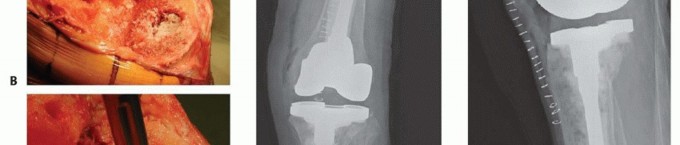

Defect Classification and Preparation

Following debridement, the tibial bone defects are formally assessed and classified according to the Anderson Orthopaedic Research Institute criteria. The intramedullary canal of the tibia is sequentially reamed to determine the appropriate diameter and length of the diaphyseal stem required to bypass the metaphyseal defects and achieve stable cortical engagement in Zone 3.

The preparation of the defect depends on the planned reconstruction method. For contained defects, the sclerotic margins of the cavity are burred or drilled to expose a vascular bed capable of supporting graft incorporation. For uncontained defects slated for structural allografting, the host bone is typically prepared with a flat planar cut or a step cut to provide a stable, geometric seating surface for the allograft.

Structural Allografting for Uncontained Defects

Massive uncontained defects (Anderson Orthopaedic Research Institute Type 3) lacking a peripheral cortical rim require structural support. While highly porous metal cones have largely supplanted bulk allografts in modern practice due to their ease of use and reliable osseointegration, structural allografts remain a vital tool, particularly in younger patients where the restoration of bone stock is a primary objective.

A fresh frozen femoral head or distal femoral allograft is selected. The host bone is prepared by resecting the remaining structurally incompetent bone to a flat, bleeding surface. The allograft is then meticulously shaped to match the host defect perfectly. The "seven up" technique is frequently used, where the graft is shaped into a figure seven to sit on the prepared host ledge while allowing the intramedullary stem to pass centrally.

The structural allograft is temporarily secured to the host tibia using Kirschner wires. The allograft host construct is then reamed as a single unit to accept the diaphyseal stem. Definitive fixation of the structural allograft to the host bone is typically achieved with interfragmentary lag screws or by the press fit interference of the diaphyseal stem passing through both the graft and the host diaphysis.